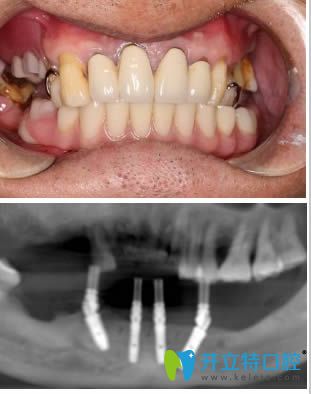

本人種牙前的樣子,如下圖:

在早些年,我的下頜牙幾乎都掉了,當(dāng)時(shí)貌似沒聽說過什么種植技術(shù),就做了活動(dòng)義齒。說實(shí)話,這些年我沒有少受假牙的折騰......來到洛陽拜博口腔經(jīng)過CT檢查完,醫(yī)生說由于我下頜長(zhǎng)時(shí)間佩戴活動(dòng)假牙,下頜骨后牙區(qū)的牙槽骨吸收較多,醫(yī)生建議我進(jìn)行手術(shù)導(dǎo)板種植,下頜多余留牙采用即拔即種。

術(shù)后影像及半口即刻種植牙一年后的樣子:

經(jīng)過這次種植牙經(jīng)歷,說心里話,我有點(diǎn)后悔.....后悔沒有在早些年來做種植牙,害的我遭受了戴假牙的后遺癥。自從種做完半口種植牙后,吃蘋果、啃排骨真是和真牙一樣,想吃什么吃什么.....這一年以來,讓我享盡了口福啊。